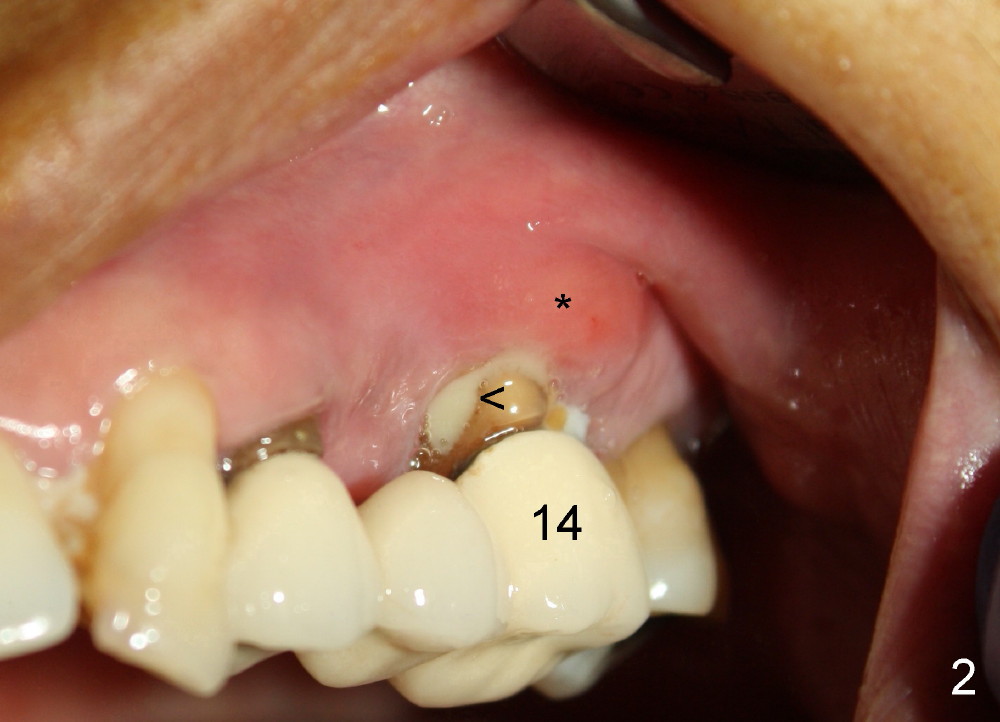

A 53-year-old lady has a failing bridge (Fig.1). There is severe bone loss around the buccal roots of #14 (*). Purulent discharge is from the gingival sulcus (Fig.2 <) with localized gingival erythema and edema (*). When the bridge is removed, the tooth #12 is found nonsalvageable (Fig.3,4). These two teeth are to be replaced by immediate implants (Fig.5). Although the sinus floor is low buccally (arrowheads), a 6x14 mm gingiva-level implant can be placed in the septum close to the palatal socket or in the palatal socket at the site of #14.